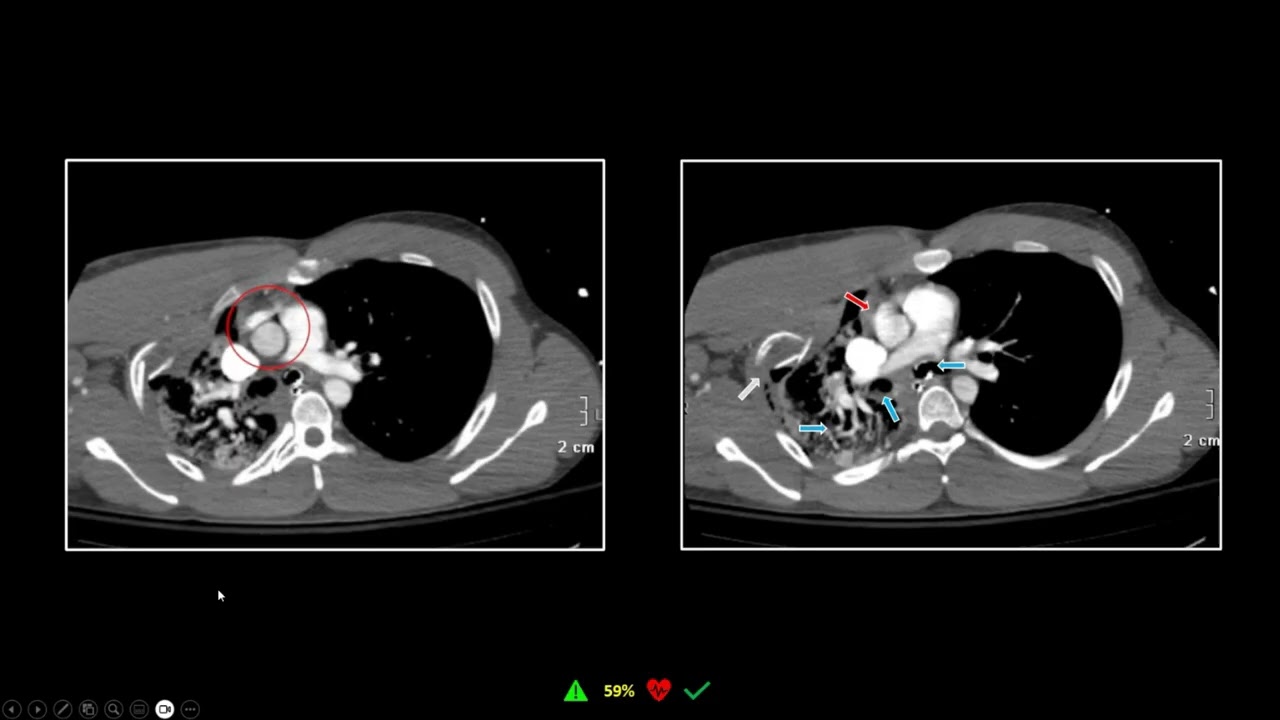

Травма кишечника | Интересные случаи в рентгенологии

В этом динамичном обзоре клинических случаев главный врач vRad, доктор Бенджамин В. Стронг, использует кинематографические и статичные изображения для анализа результатов и диагностики некоторых из своих любимых случаев, взятых из обширной учебной библиотеки vRad.

Ознакомьтесь с типами острого повреждения кишечника. Определите, какие результаты КТ полезны для диагностики и лечения острого повреждения кишечника. Распознайте подводные камни визуализации, которые могут привести к пропуску или неверной интерпретации результатов КТ острого повреждения кишечника.

Диагнозы: разрыв желудка, разрыв двенадцатиперстной кишки, ушиб кишечника, эвисцерация, ишемия, ушиб толстой кишки, разрыв прямой кишки.